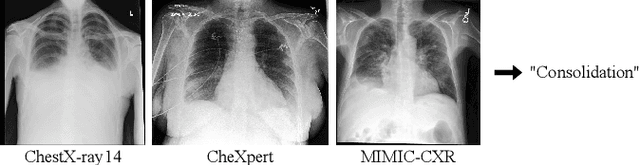

While deep learning models become more widespread, their ability to handle unseen data and generalize for any scenario is yet to be challenged. In medical imaging, there is a high heterogeneity of distributions among images based on the equipment that generate them and their parametrization. This heterogeneity triggers a common issue in machine learning called domain shift, which represents the difference between the training data distribution and the distribution of where a model is employed. A high domain shift tends to implicate in a poor performance from models. In this work, we evaluate the extent of domain shift on three of the largest datasets of chest radiographs. We show how training and testing with different datasets (e.g. training in ChestX-ray14 and testing in CheXpert) drastically affects model performance, posing a big question over the reliability of deep learning models.